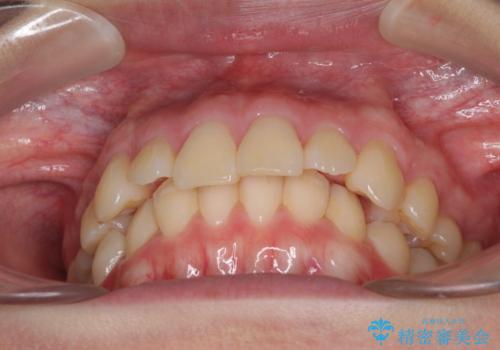

上顎前突 目立たないワイヤー装置での抜歯矯正

- 口元の突出感改善を希望して来院された患者様です。

口元を積極的に引っ込めるために、上下左右の小臼歯計4本を抜歯することとしました。

咬み合わせが深いため、咬み合わせの高さを向上させながら口元を下げることとしました。

左右ともに下顎に対して上顎歯列が前方位にある上顎前突であったので、上顎歯列全体を後方に移動させることで上下咬み合わせを改善し、その上で抜歯矯正により口元の突出感を改善させていきました。